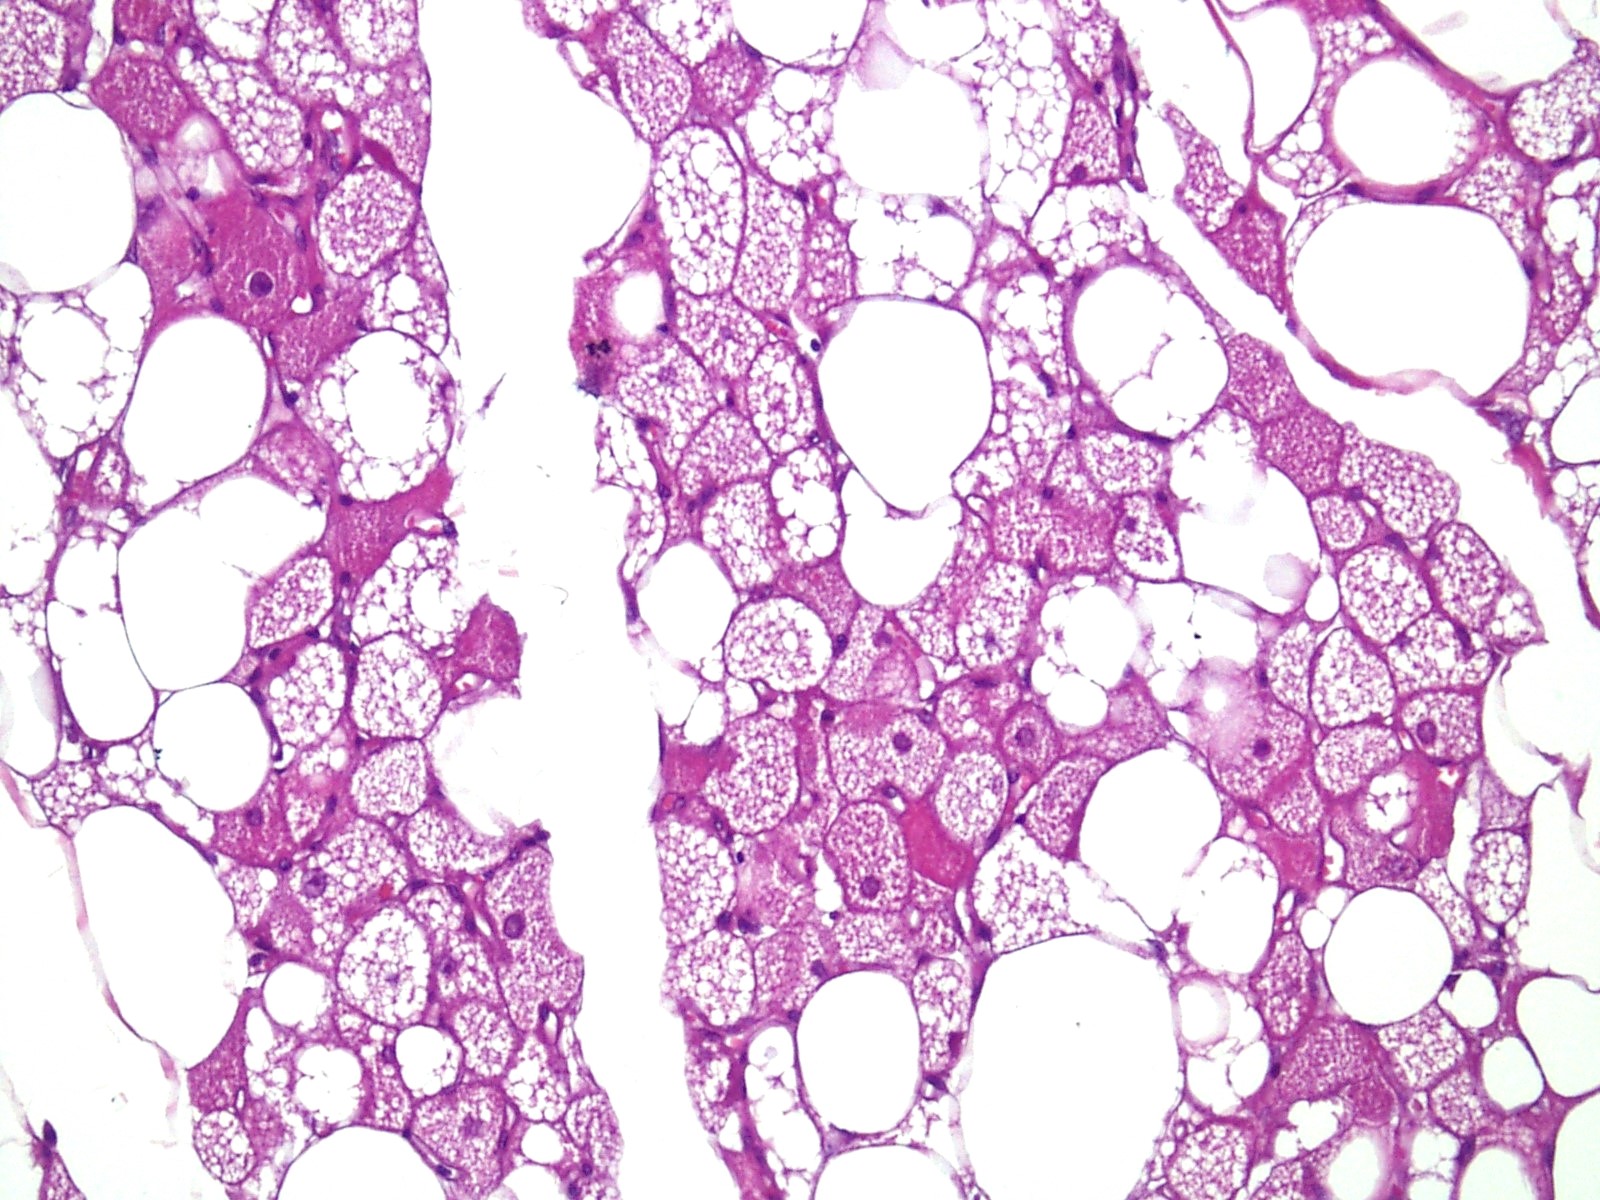

Microscopic (histologic) description

- Neoplastic lesion composed of polygonal brown fat cells with stromal cells in the background (Case Rep Oncol 2017;10:438)

- Large number of pale and eosinophilic brown fat cells with multivacuolated, eosinophilic granular cytoplasm and small central nucleus (about 70%) admixed with variable amount of univacuolated white cells (Case Rep Oncol 2017;10:438, Am J Case Rep 2020;21:e921447, J Comput Assist Tomogr 2019;43:793, J Pathol Transl Med 2017;51:499, Am J Surg Pathol 2018;42:951, Virchows Arch 2021;478:527)

- Multivacuolations resemble lipoblasts

- Morphological variations or subtypes: typical, myxoid (9%), lipoma-like (7%), spindle cell (2%), thick bundles of collagen fibers, presence of mast cells and exclusively containing brown fat cells (Case Rep Oncol 2017;10:438, Am J Case Rep 2020;21:e921447, Virchows Arch 2021;478:527)

- Cytological atypia, necrosis and mitosis is unusual (J Pathol Transl Med 2017;51:499, Am J Surg Pathol 2018;42:951, BMC Surg 2021;21:30)

Microscopic (histologic) images